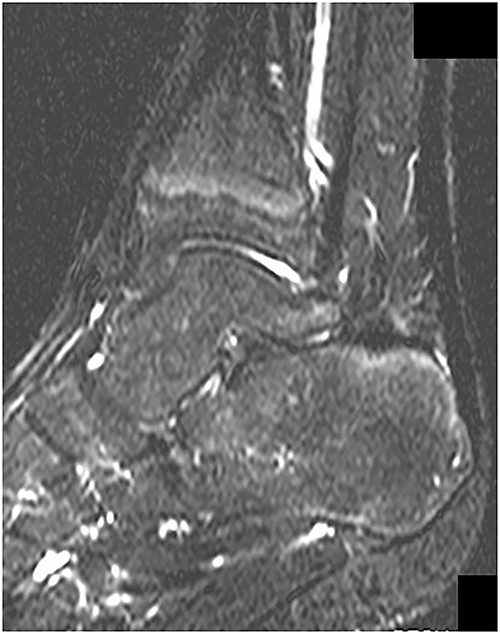

MRI demonstrated a low intensity signal (arrow) on (A) T1-weighted images and a high intensity signal (arrow) on (B) T2-weighted images in the retrocalcaneal bursa.